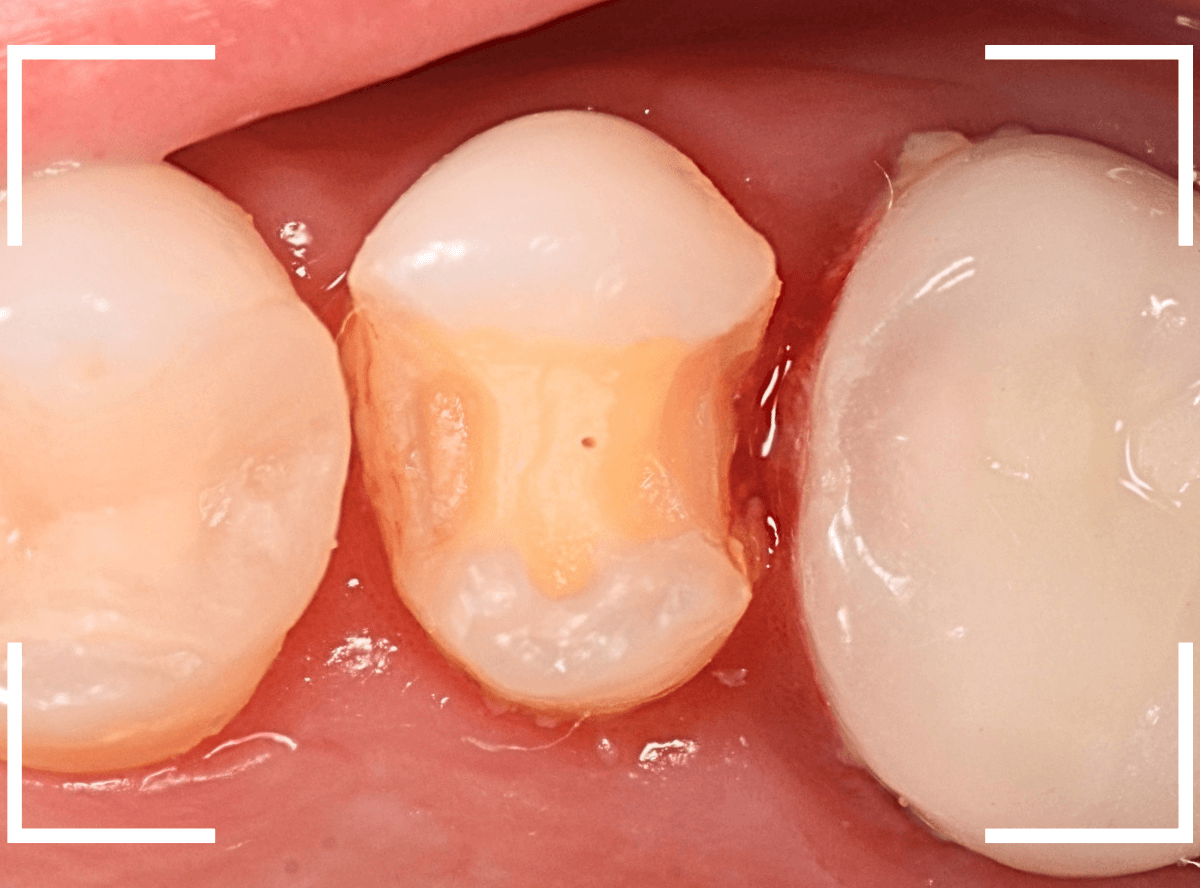

虫歯の治療を開始します。

隣の歯とのすき間を中心に広い虫歯になっていました。

虫歯治療後、特に症状もなく経過観察できましたので、つめものを作る治療に入ります。